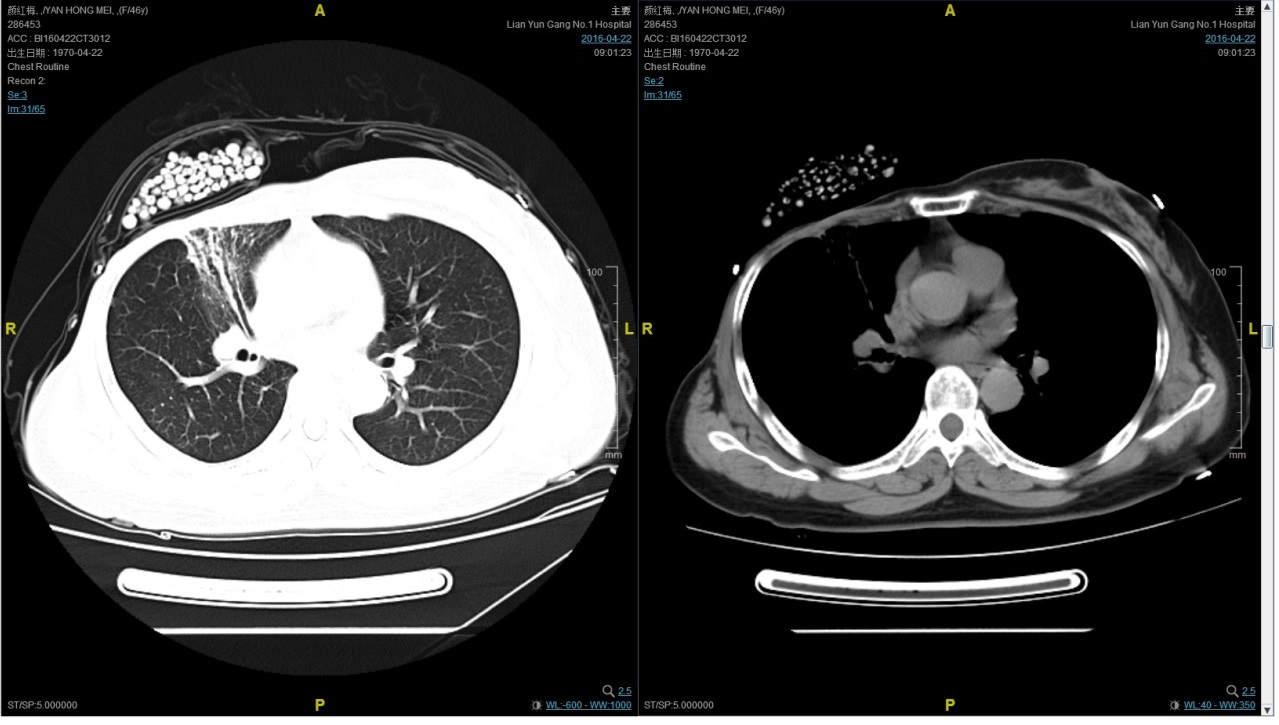

期间2016-4-22复查CT如下:

2016-7-5化疗结束后复查CT,疗效评价稳定。